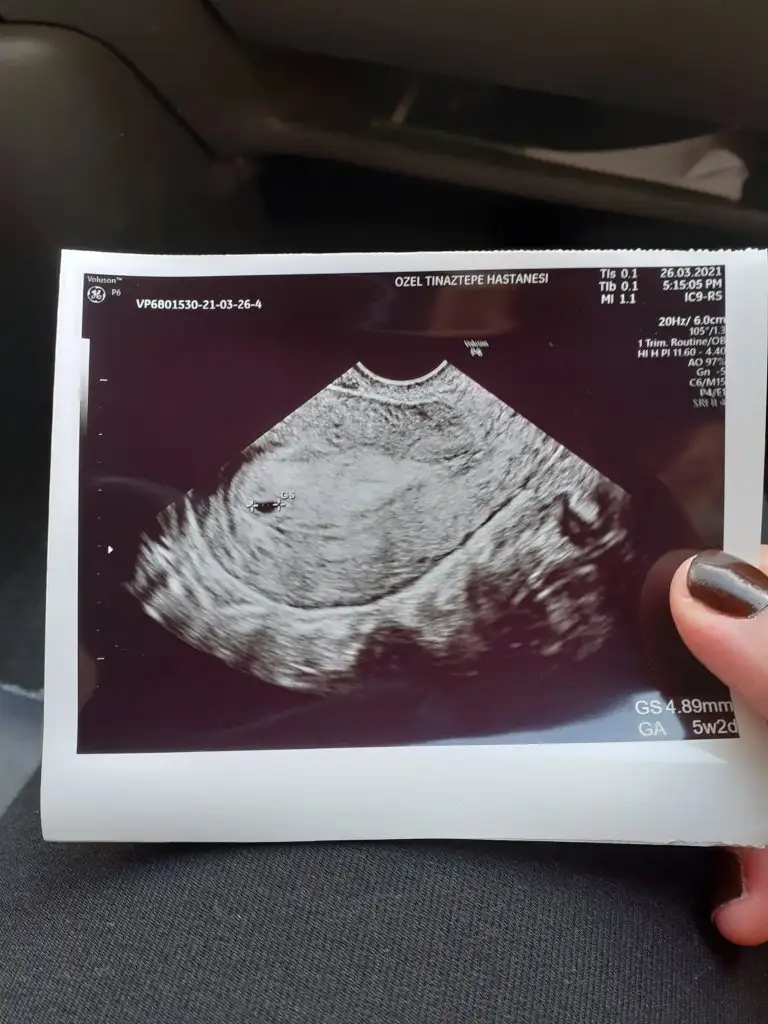

Ramzi teorisine göre cinsiyet tahmini yapacagim ilk ultrasyon resminizi atin bakiyim. Eger cinsiyetiniz belliyse hic söylemeeyin bakalm dogru tahmin edebilecekmiyim daha dogrusu ramzi teorisi hakli cikacak mi?

Benim ultrason karından ama yinede tam anlayamıyorum sağ-sol nasıl olduğunuVajinal ultrasonda bebek kesenin sol tarafında ise kız sağda ise erkek yazıyor internette, karından ultrasonda tam tersi solda ise erkek sağda ise kız yazıyor. Bende daha önce buraya yazdım yorum yapılmayınca araştırdım sizinde bilginiz olsun basit yani kendimizde bakınca anlayabiliriz

Karından ultrasona göre benimki sol da mı duruyor, erkek mi oluyorVajinal ultrasonda bebek kesenin sol tarafında ise kız sağda ise erkek yazıyor internette, karından ultrasonda tam tersi solda ise erkek sağda ise kız yazıyor. Bende daha önce buraya yazdım yorum yapılmayınca araştırdım sizinde bilginiz olsun basit yani kendimizde bakınca anlayabiliriz

Erkek yerinde benim arkadasimin ultrasonuyla ayni yerde onun erkegi olduKarından ultrasona göre benimki sol da mı duruyor, erkek mi oluyor

KarındanAlttan

Karından canımKarindan mi alttanmi muayene